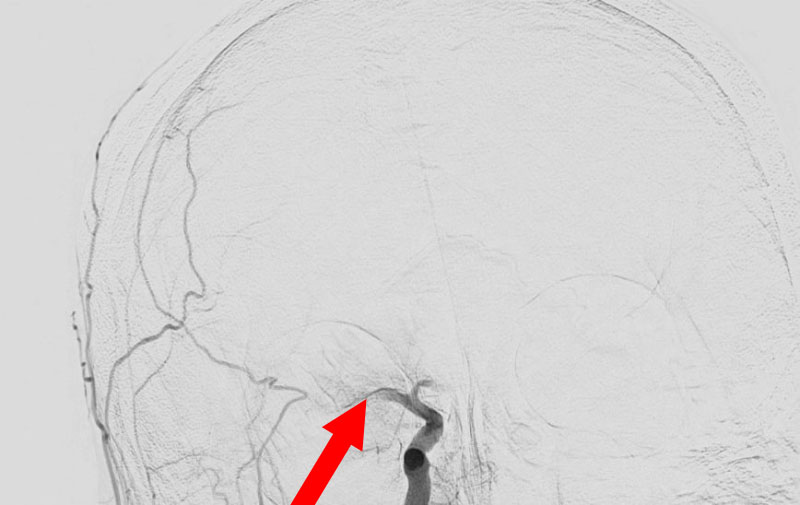

くも膜下出血

右内頚動脈後交通動脈

分岐部動脈瘤破裂

60代

救急外来

No.1593 手術前

No.1593 手術中

No.1593 手術後